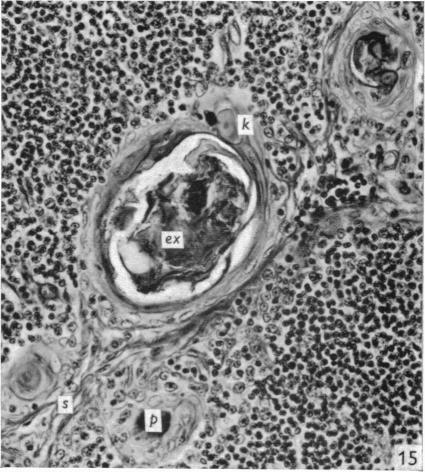

The effect of castration, oestrogens, testosterone and the oestrous cycle on the cortical epithelium of the thymus in male and female rats.

J Anat. 1968 Jun;103(Pt 1):113-33.